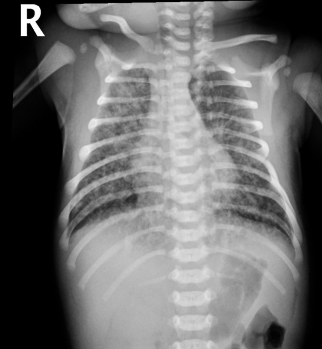

infiltrates, flattening, supportive, nitric oxide

Meconium Aspiration Syndrome: CXR and Treatment

-CXR → patchy ________, overdistention (increased AP diameter), and ________ of the diaphragm

-Treatment → _________ care and assisted ventilation. In the case of persistent severe hypoxia, you could try surfactant therapy, inhaled ______ ______, or ECMO